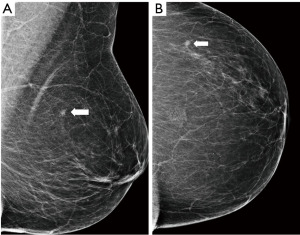

- Screening, an asymptomatic woman of 65 years old, in mammography an architectural distortion is detected in the lateral part of the left breast. The ultrasound findings are subtle with suggested areas of decreased echogenicity. The biopsy under ultrasound guidance reveals DCIS grade 2. The extent of the disease however is not certain. MRI is indicated. MRI shows an extensive process in the lateral part of the left breast resulting in the need of mastectomy (Figure 10).

Figure 10 Mammography of the left breast in cranio-caudal view (A) with architectural distortion (arrow). The distortion is more visible in DBT (B) (arrow). Ultrasound (C) reveals subtle finding of irregular area of decreased echogenicity (arrow). MRI (D) shows extensive area of non-mass-like enhancement in the whole lateral part of the breast (arrow). DBT, digital breast tomosynthesis; MRI, magnetic resonance imaging. - Diagnostic assessment, a patient of 45 years of age with a palpable lump on the right side for 2 months. In mammography with higher proportion of fibroglandular tissue (category C) several areas of increased density with irregular margins and architectural distortions are visible. Ultrasound confirms more than one lesion. MRI demonstrates a large area of enhancement up to 7 cm (Figure 11).